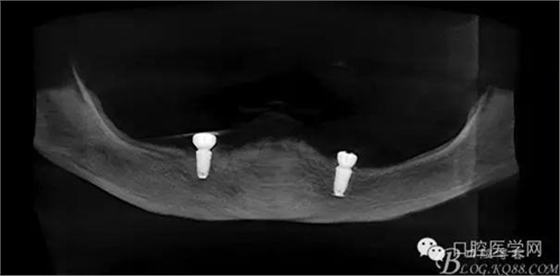

種植體植入后

種植覆蓋全口義齒3個(gè)月后上球型基臺(tái)